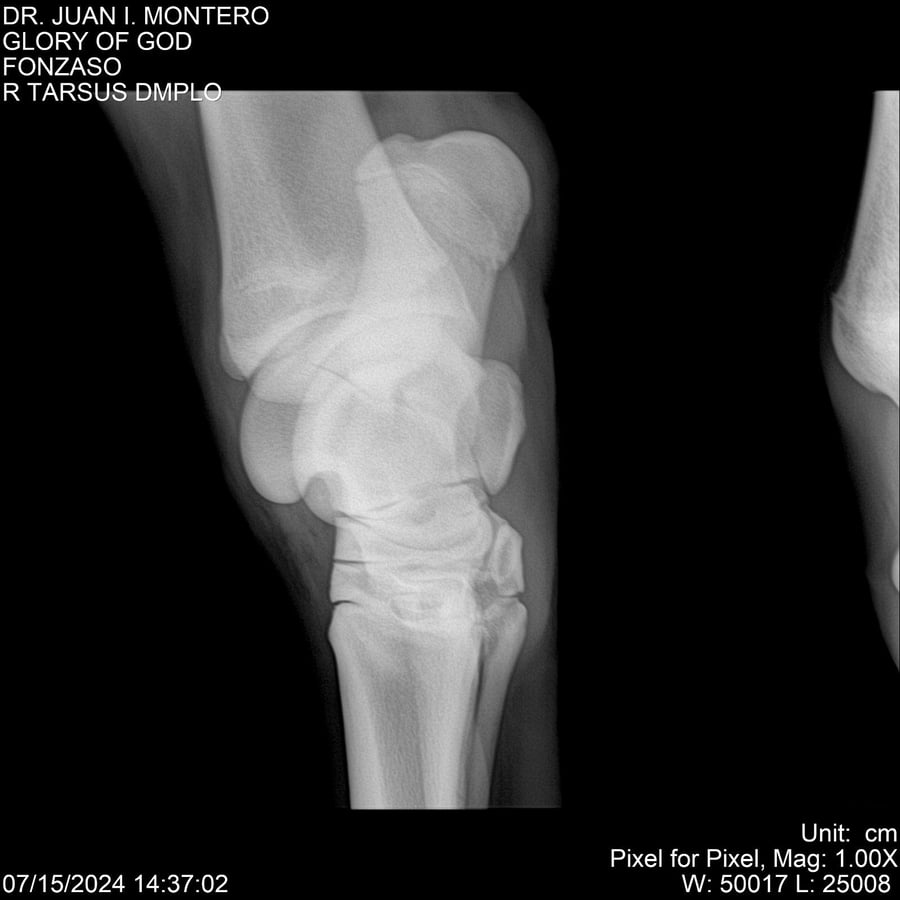

LOTE 10, GLORY OF GOD 🔥 🔥 🔥 Lote Anterior Volver al remate Lote Siguiente Ficha Contacto Montevideo - Ficha del Lote Identificador: #281389 Categoría: Yeguarizos Montevideo - 115 Visualizaciones ClicData Contacto Empresa: Abelenda N. R., Walter Hugo Nombre*: Teléfono* : E-mail* : Mensaje Enviar Registrese gratis Este contenido Exclusivo está disponible sólo para usuarios registrados Ingresar